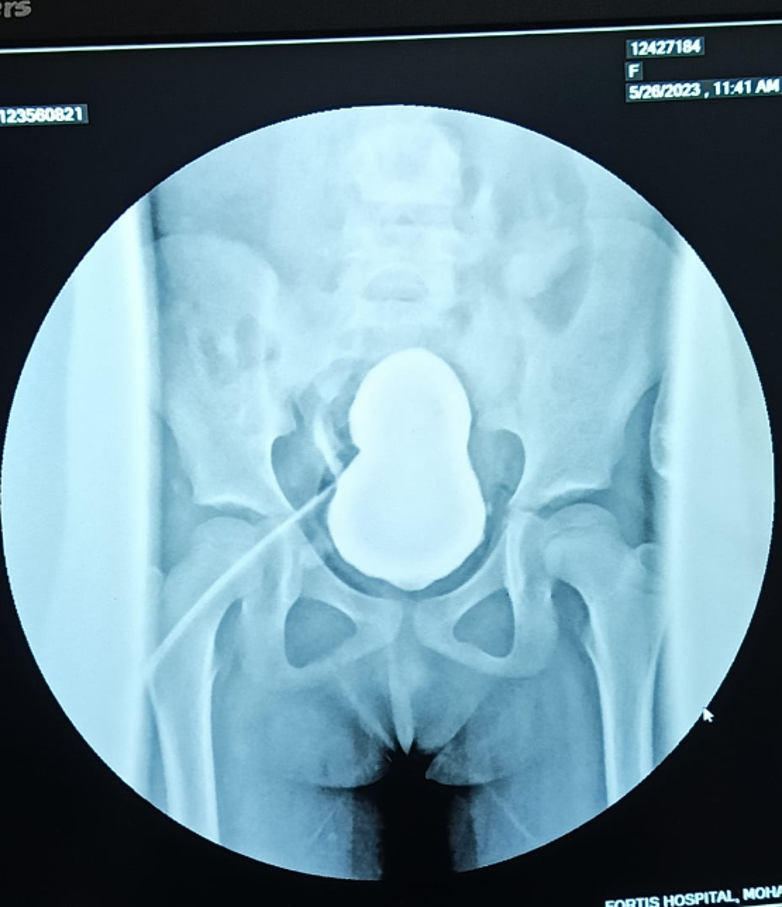

DSA (digital subtraction angiography) study was suggestive of chronic thrombosis of Infra-renal IVC (Inferior Vena Cava) extending to the right external iliac vein, likely related to the tunneled dialysis catheter. Her immunological workup was negative for any Donor Specific Antibodies. She was planned for a kidney transplant with her mother as the donor. Graft Kidney was implanted intraperitoneally onto the left common iliac vessels followed by bladder augmentation and a continent urinary diversion. Her post-operative course was uneventful with an adequate functioning allograft. She was discharged with a serum creatinine of 0.3 mg/dl on post-operative day 9. She is maintaining a good urine output of 2.5-3 liters through the diversion stoma at 3 weeks.